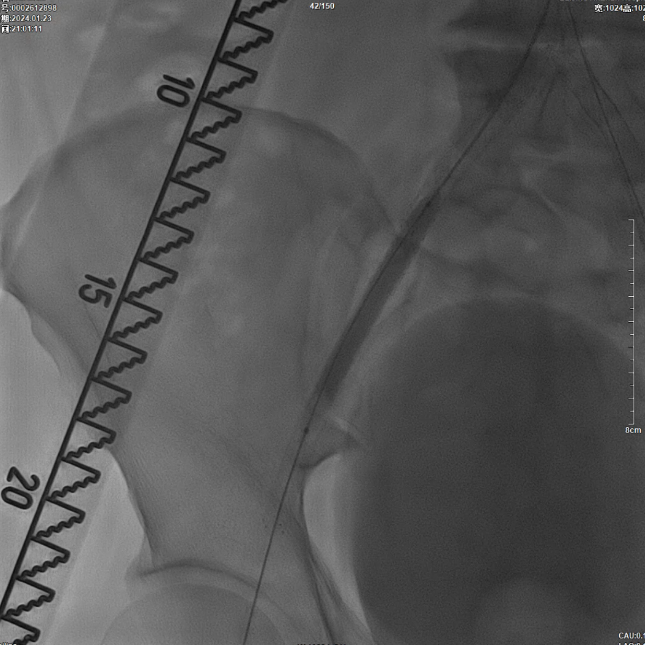

髂动脉重建

CERAB技术关键点二:先用14mm×40mm球囊分别扩张双侧髂肢的腹主动脉段。

再用8mm球囊对双侧髂支腹主动脉段行对吻扩张,以确保双侧髂支与腹主动脉覆膜支架腔内获得良好的贴壁形态,最大程度减少空腔,降低远期再狭窄发生率。

右侧髂外动脉存在残存狭窄,因该部位无原有裸支架覆盖,为节省治疗费用,选择植入1枚直径8mm的裸支架,并采用8mm球囊进行后扩张。